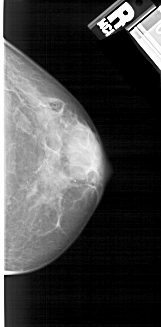

A_1937_1.LEFT_MLO

LEFT_MLO LINES 5491 PIXELS_PER_LINE 2221 BITS_PER_PIXEL 12 RESOLUTION 43.5 OVERLAY